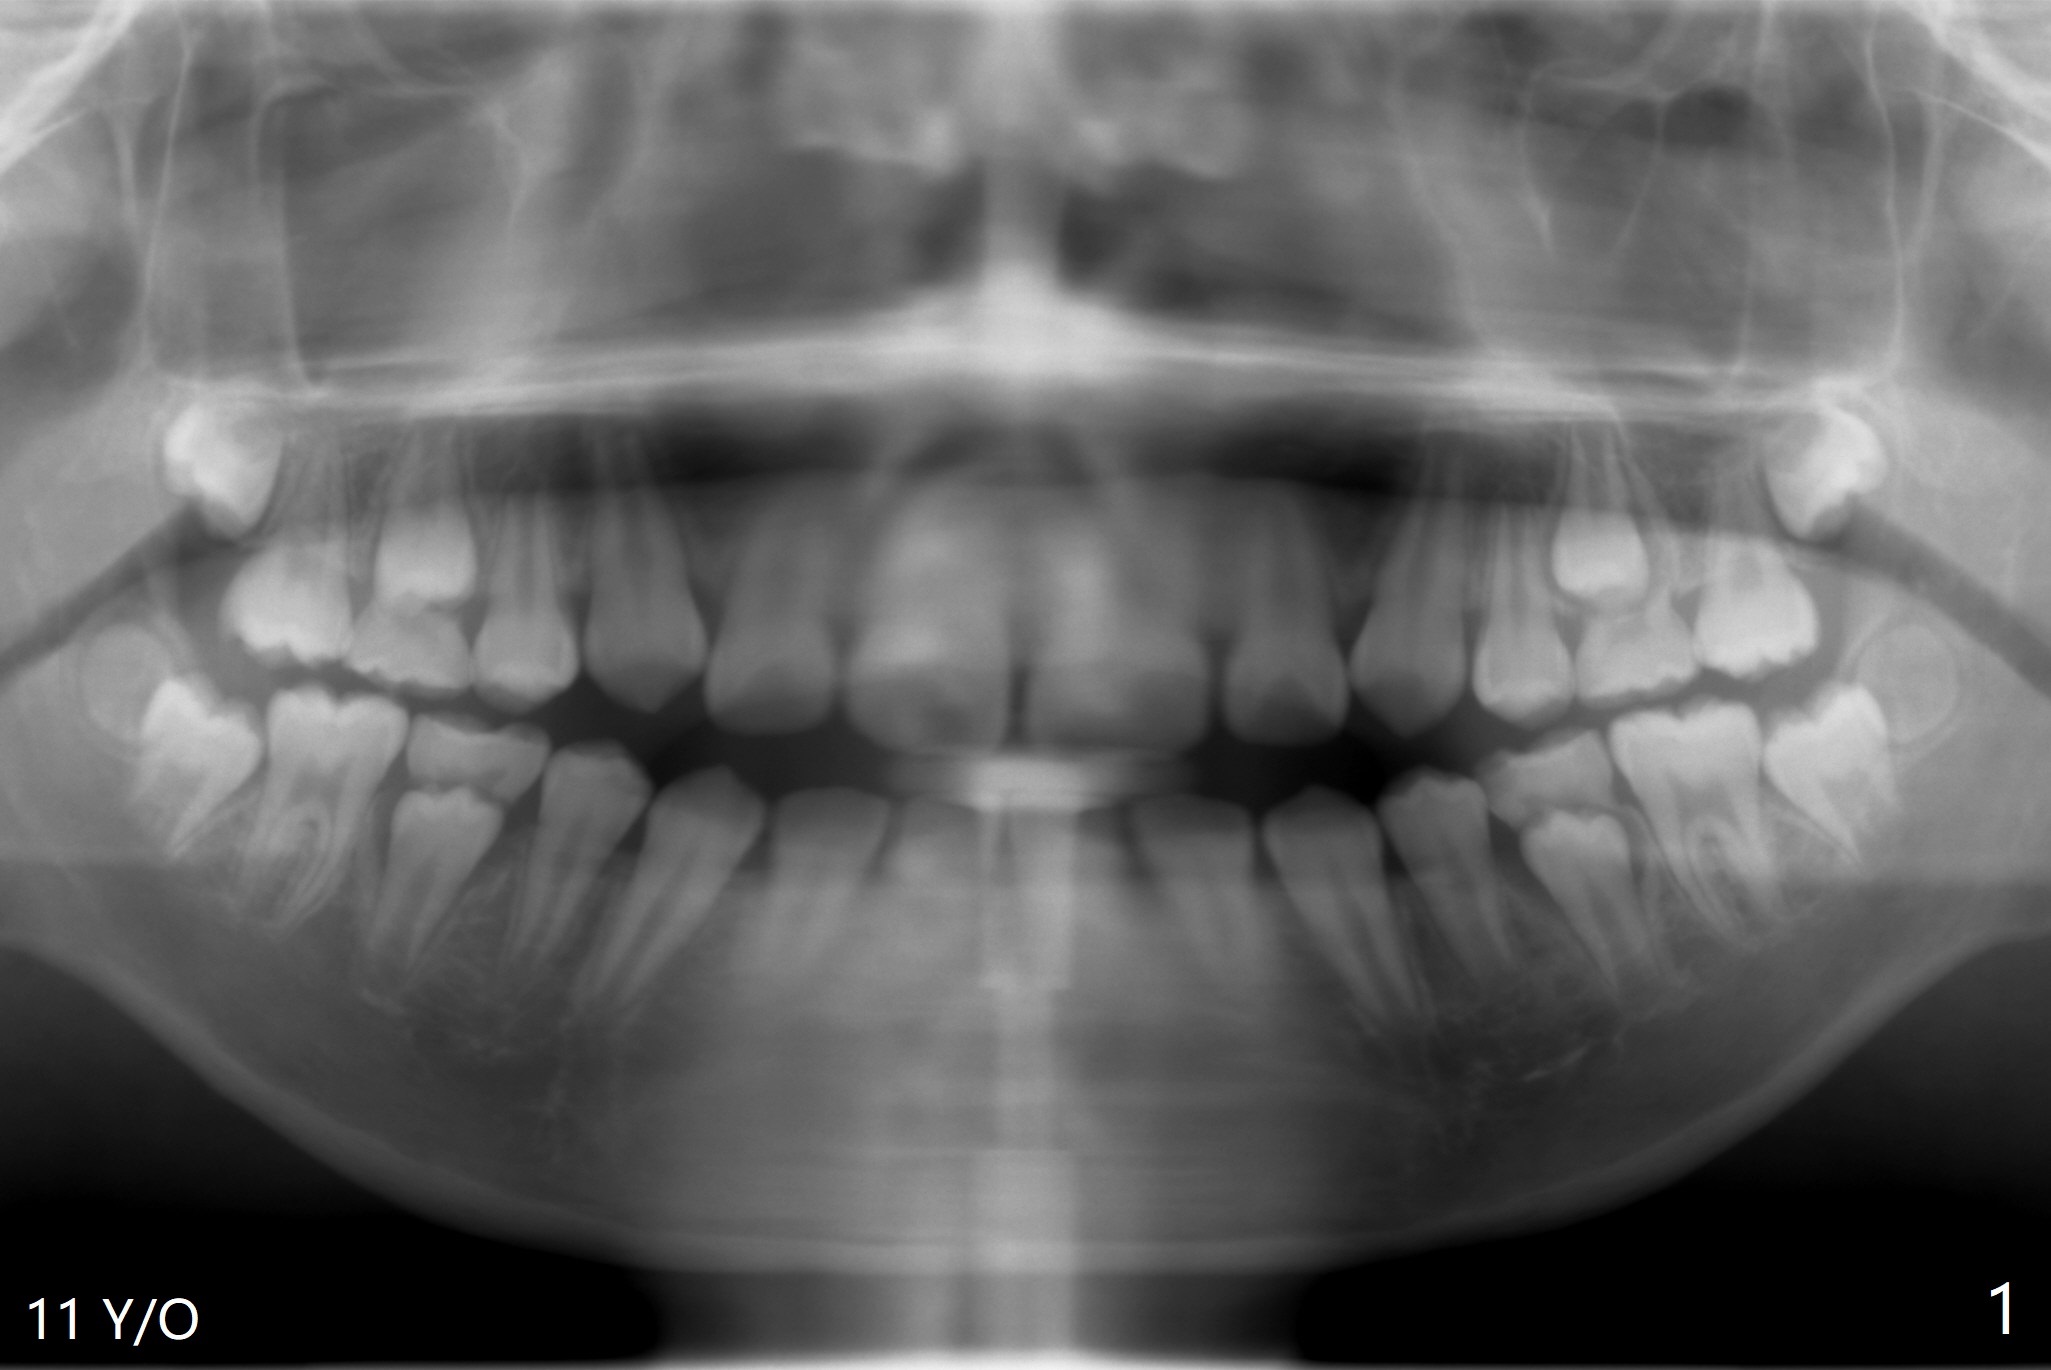

The teeth #17 and 32 are developing at the age of 11 of a woman (Fig.1). She requests extraction at the age of 20 (Fig.2 (anterior open bite)). While buccodistal trough is created for both of them, the one at #32 needs a sectioning before removal. Osteogen plug is applied for both of them. Postop hemorrhage occurs at #32 for 2 days.